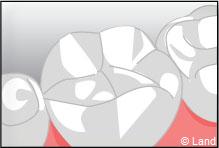

L’onlay intéresse aussi la surface occlusale (masticatoire) de la dent.

Exemple d’un onlay molaire